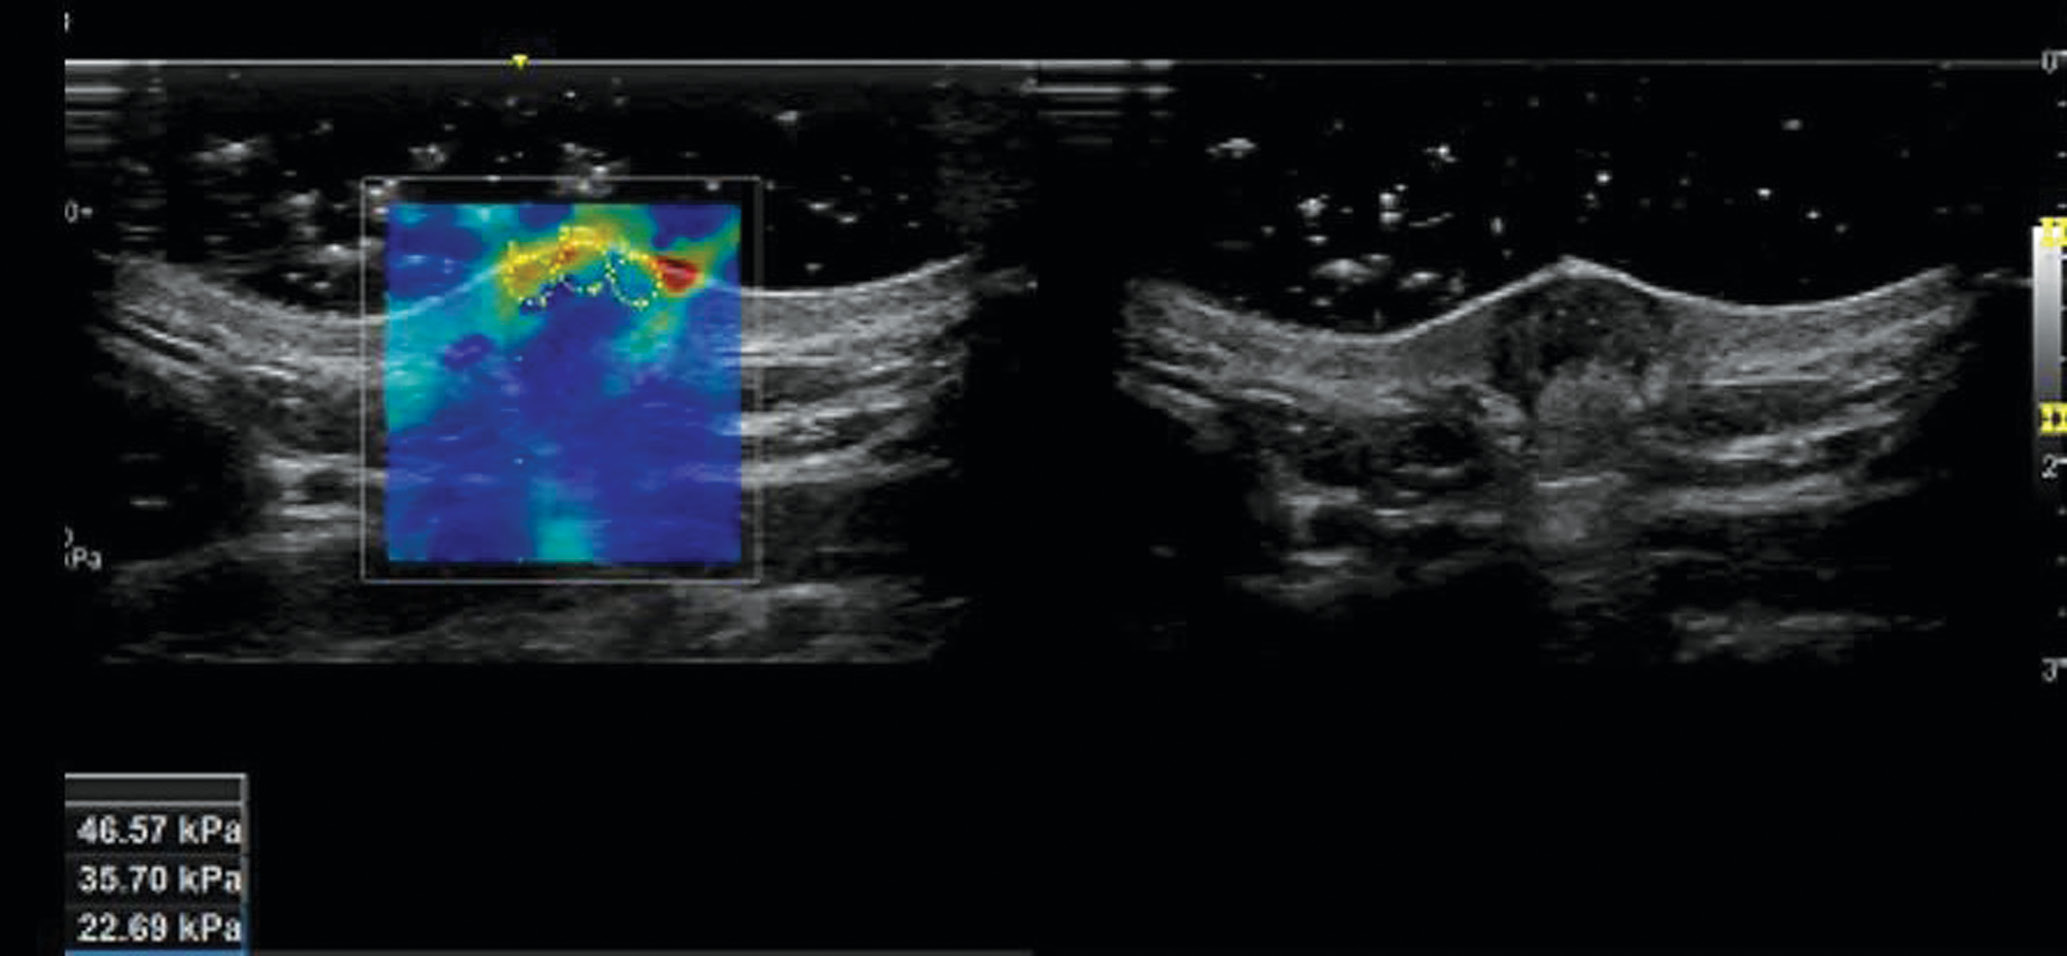

Эластографию сдвиговой волны проводили на ультразвуковом аппарате Logic 9 с линейным датчиком L3–L12 в режиме эластографии. Полученная эластограмма представляет собой цветовую кодировку, которая накладывается на изображение в В-режиме. Красный цвет представляет собой более жесткие области, а синие — более мягкие. Цветовой шкале соответствует количественный показатель, измеряемый в килопаскалях. Выполнялось 4–5 снимков в зависимости от наличия артефактов на эластограмме. Далее оператор выбирал снимок и производил три замера жесткости по ходу рубца с вычислением среднеарифметического итогового показателя (рис. 3). Аналогично проводилась оценка на участке здоровой ткани. В ходе работы была разработана гелевая подушка, которая минимизировала давление на ткани, создавая акустическое окно между исследуемым участком и датчиком (рационализаторское предложение № 15461/8 от 19 октября 2023 г., принято к использованию Военно-медицинской академией) (рис. 4).

Рис. 3. Эластография гипетрофического рубца кожи голени у женщины 19 лет: слева —эластограмма; справа — этот же рубец в В-режиме

Fig. 3. Elastography of a hypetrophic scar of the skin of the tibia in a 19-year-old woman: on the left — the elastogram; on the right — the same scar in B-mode